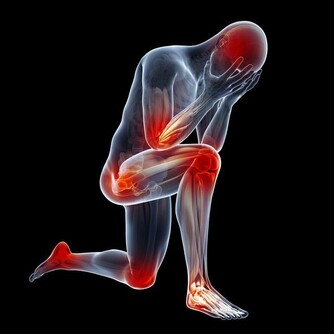

高尿酸除了傷害關節外,也會連累心血管系統和腎臟,因此應積極控制尿酸,其含量不能超過360微摩爾。少吃或不吃高嘌呤食物,多喝白開水,堅持運動來降低尿酸濃度;同時應定期做腎臟B超、腎功能檢查,用於評估腎臟是否健康。